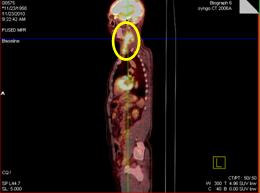

Hình ảnh PET/CT trước và sau điều trị

Hình 4: Trước điều trị: Hình ảnh khối hạch vùng cổ trái kích thước 10x12 cm, tăng hấp thu FDG mạnh (vòng tròn vàng).

Hình 5: Sau điều trị 4 tháng (6 chu kỳ hóa chất) : hình ảnh chụp PET/CT sau điều trị cho thấy khối hạch cổ trái tan biến hoàn toàn, không thấy tăng hấp thu FDG tại cơ quan bộ phận khác của cơ thể.

Hình 6: Sau điều trị 6 năm: hình ảnh chụp PET/CT sau điều trị cho thấy khối hạch cổ trái tan biến hoàn toàn, không thấy tăng hấp thu FDG tại cơ quan bộ phận khác của cơ thể.